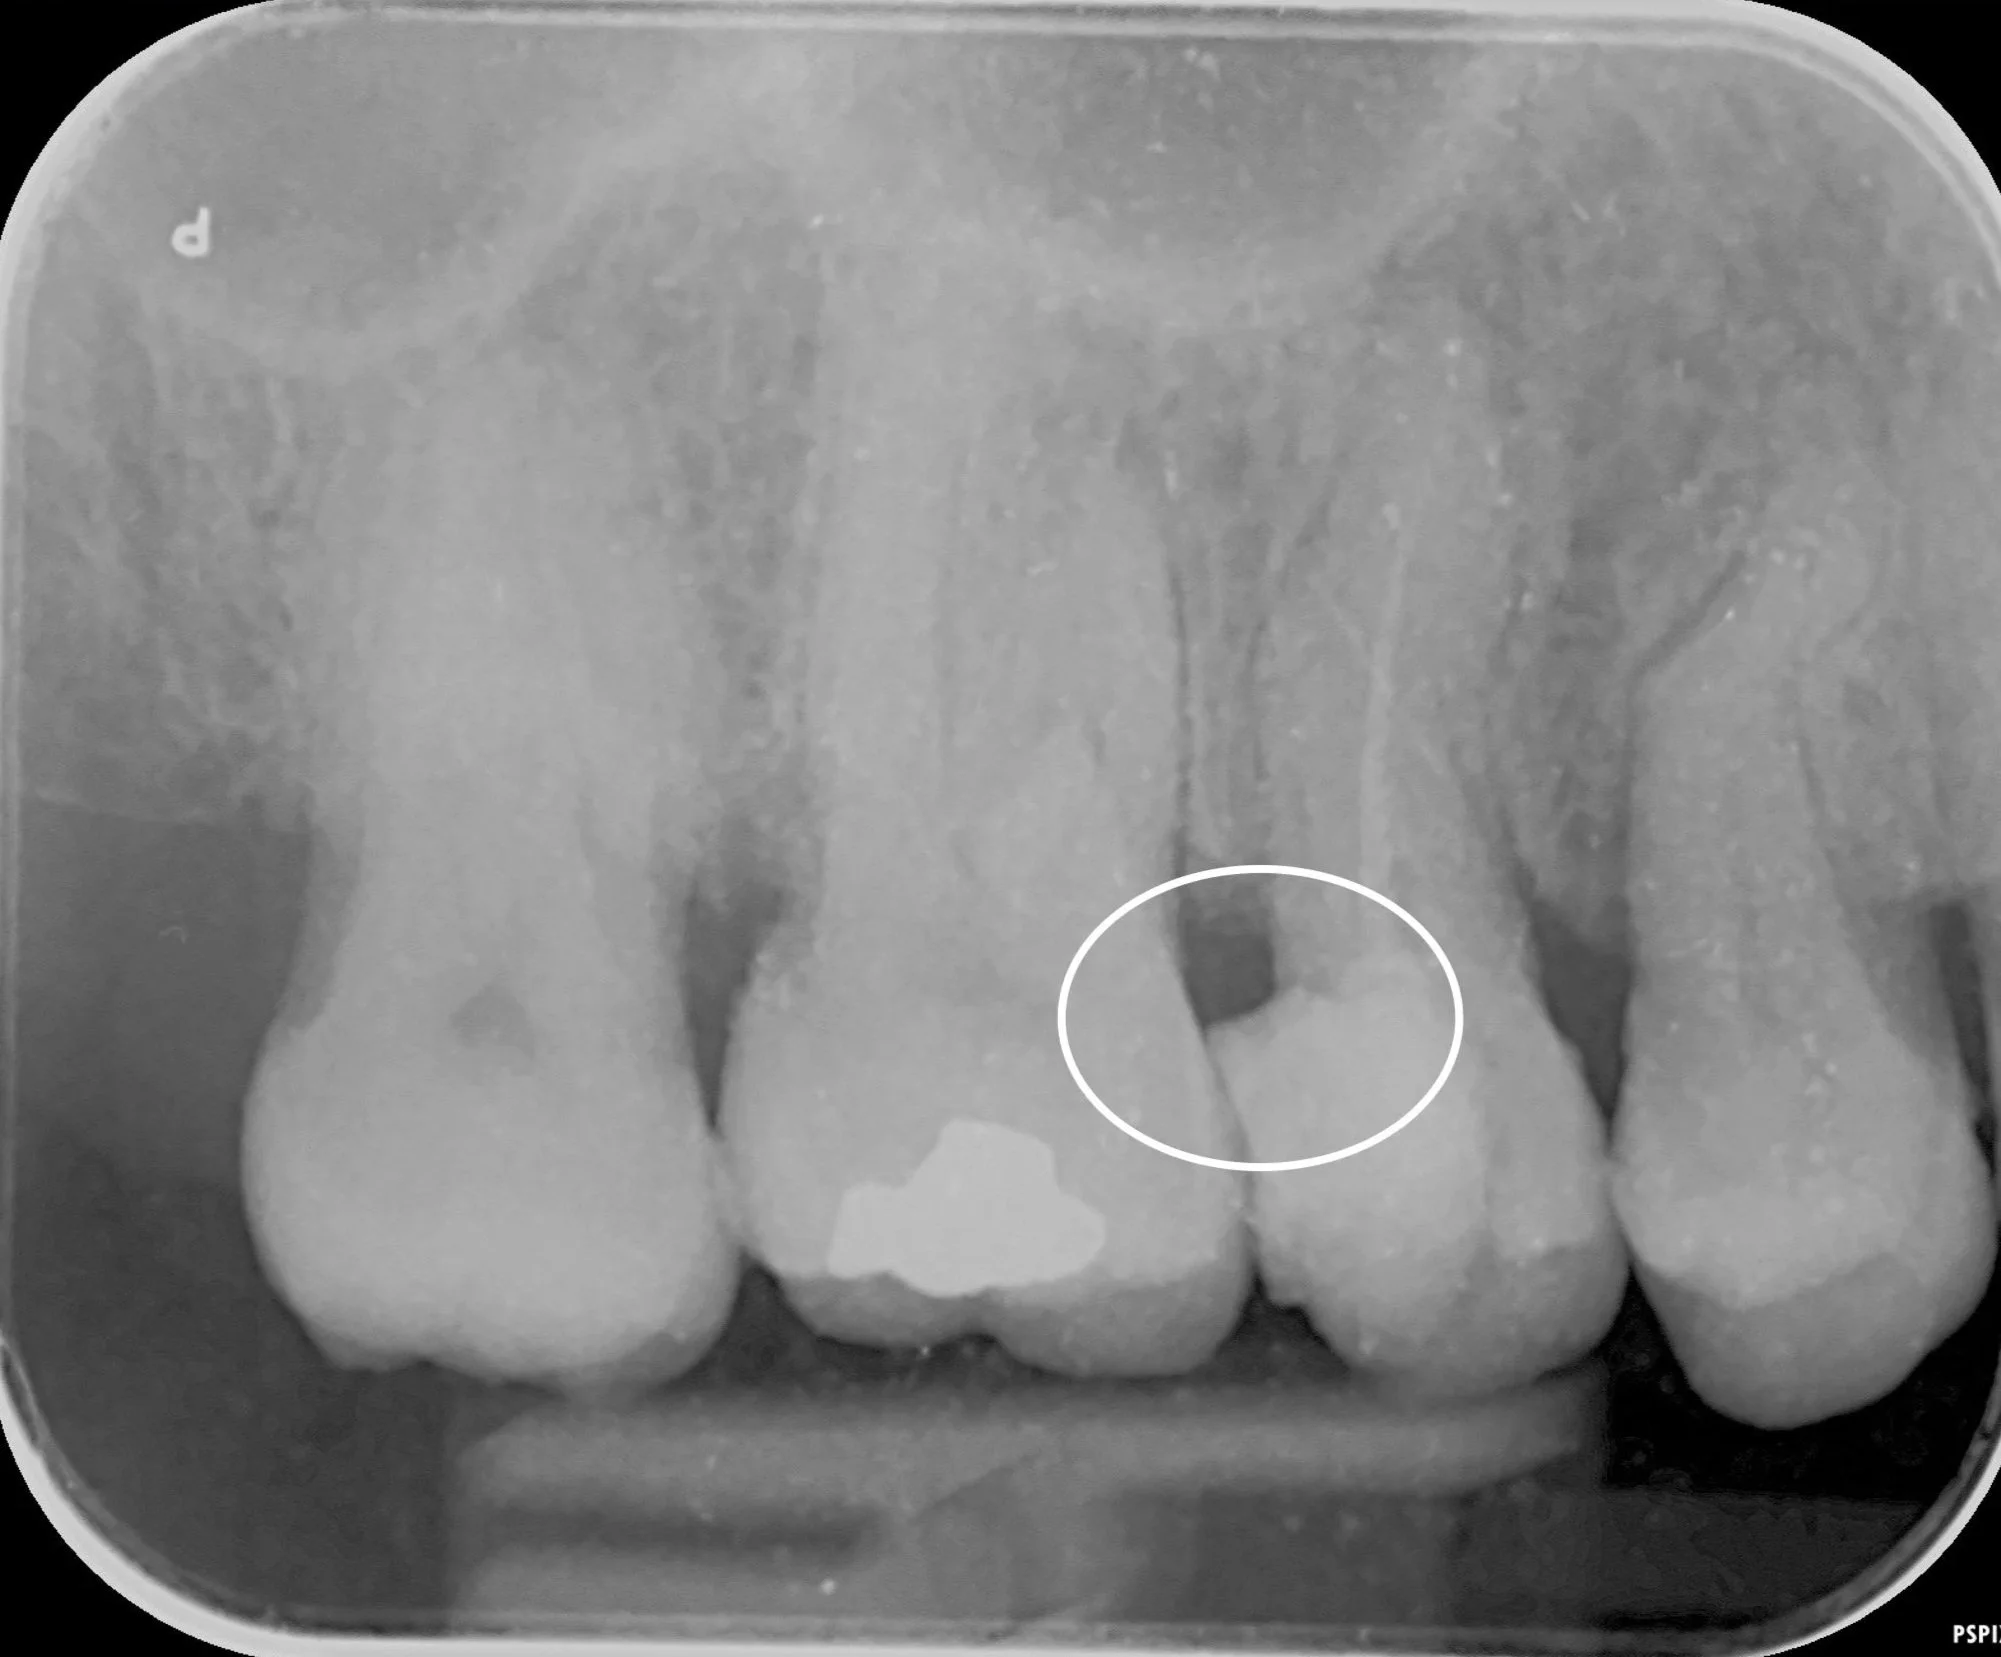

An x-ray showing 2 fillings with good flush smooth margins and a healthy contact point

What a Good Filling Should Feel Like

A well-made filling shouldn’t just look good on an X-ray; it should feel comfortable and be easy for you to keep clean every day. In most cases, you shouldn’t really notice it at all.